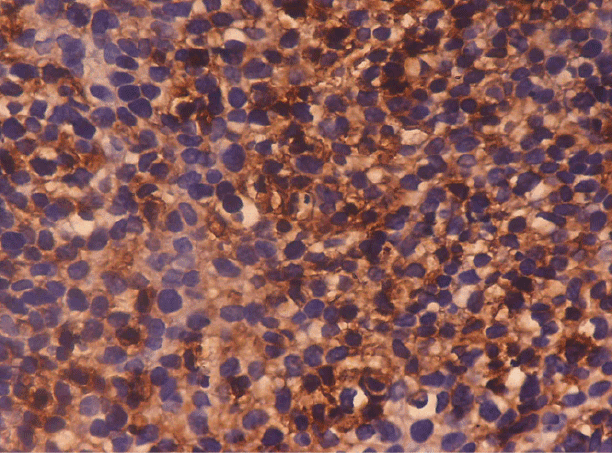

10例中,高分化9例(90.0%),中分化8例(80.0%),低分化1例(10.0%)E-cadherin为4+染色(图1)。中分化2例(20.0%),低分化2例(20.0%)。低分化癌2例(20.0%)为2+,3例(30.0%)为1+,2例(20.0%)为0。Fischer精确检验' p值' <0.05,具有统计学意义(表2)。

图1:分化良好的鳞状细胞癌:显微照片显示肿瘤细胞强烈,膜性,4+级染色。(IHC: E-cadherin × 40X)

图2:低分化鳞状细胞癌:显微照片显示癌巢中4级+细胞质染色。(IHC Vimentin × 40X)